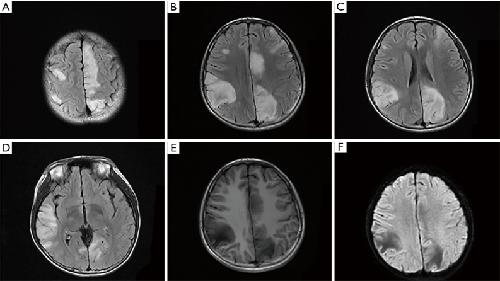

Kv3.1 channelopathy: a novel loss-of-function variant and the mechanistic basis of its clinical phenotypes., Li X, Zheng Y, Li S, Nair U, Sun C, Zhao C, Lu J, Zhang VW, Maljevic S, Petrou S, Lin J., Ann Transl Med. September 1, 2021; 9 (18): 1397. |